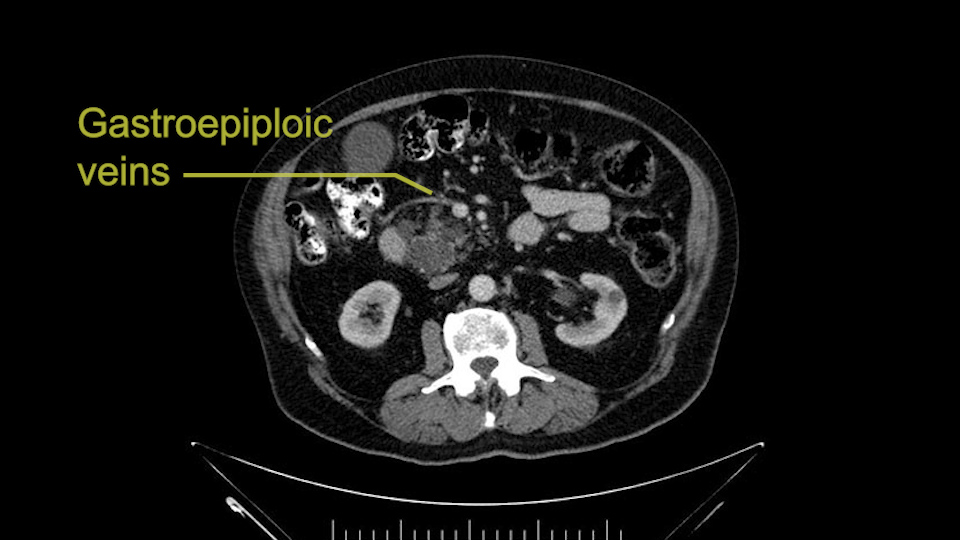

The other thing I look at is the gastroepeiploic arcade- which is this thing here- which is where the gastroepeiploic vein joins the portal vein. I call it the gateway to the neck of the pancreas because you pretty much have to divide it to get to the neck. The middle colic vein usually drains either into it or nearby. I think we’re seeing it here. Again,that can be divided and I usually divide those two and it helps me get under the neck. Again, there’s no issues here with the tumor so it’s nice from that perspective. If I was concerned about the vein, which I’m not here, I would go to the coronal view. It’s a nice way to look at the vein on just a couple of cuts and you can see a beautiful view of it here. There’s the portal vein, there’s the head of the pancreas. There’s the tumor. It’s a little closer here than it looks on the other one. I doubt it’s involved. If it’s touching, it may not be invading it but even if it was, it's a short segment. Anyways, there’s the SMV there’s the splenic vein, and everything looks good. You can see the stent. I ignore the stent. It’s the most dramatic looking thing in the picture but it’s actually the least important.

I am a believer in pylorus preservation. And in this case I see no reason why that wouldn't be possible. Mobilize the duodenum, divide the gastroepiploic vessels and divide the duodenum. I try to divide it with a linear stapler about four centimeters from the pylorus to have adequate length for my GI anastomosis. This facilitates exposure of the head neck of the pancreas. I find the gastroduodenal artery. This patient has normal arterial anatomy. Always on every preoperative CT scan I look to see if there is a replaced right hepatic. In this case I did not see one. Regardless of how confident I am I always look carefully for variant anatomy. I always do a clamp test on the GDA before ligation. I doubly ligate the GDA with not just a tie but a suture ligature because of the risk of GDA blowout in patients with a leak.